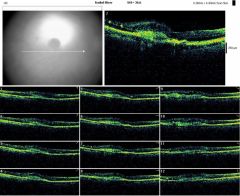

OCTOD

OCTOG